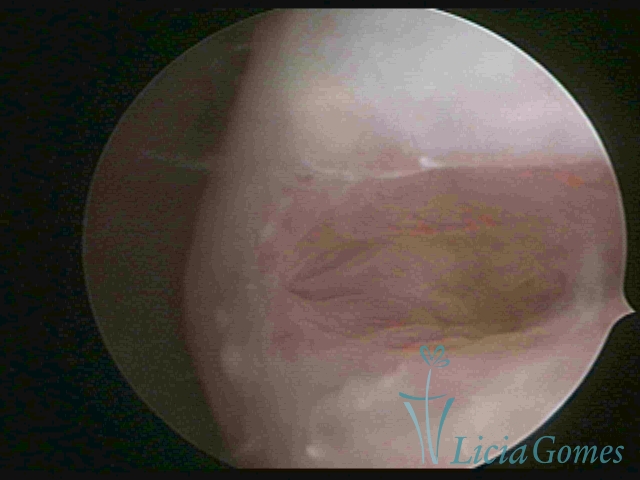

• First part or proximal section or lower section, presence of a light, crystalline mucus, presence of crypts, microvesicular (resembling grape clusters.)

• Second part or middle section: the details of the buds are lost. It is possible to view longitudinal creases.